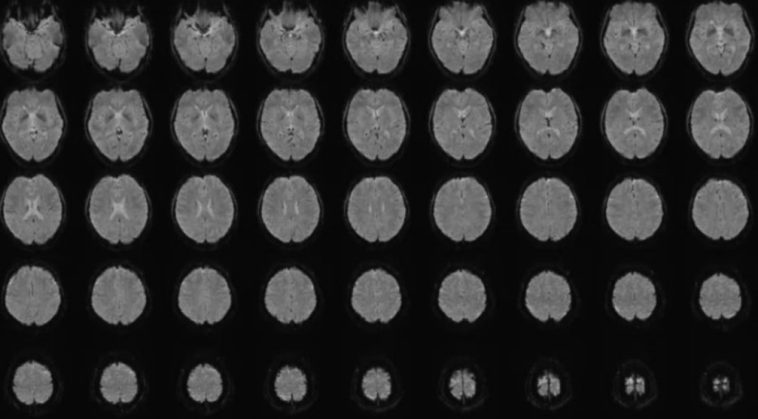

Participants were shown 2,180 short silent videos containing various scenes, including objects, nature landscapes, human actions, and daily activities. While watching the videos, their brain activity was recorded using functional Magnetic Resonance Imaging (fMRI).

- fMRI Brain Scans: Captures real-time neural activity during video observation.